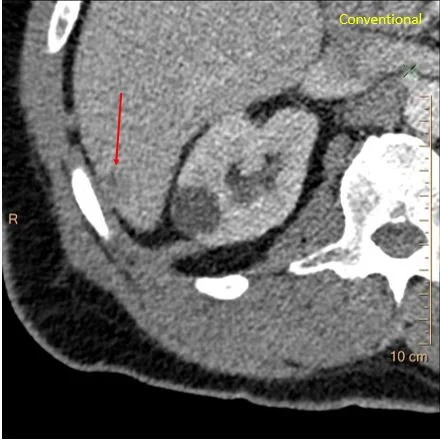

Conventional CT: The lesion in the liver is very hard to see.